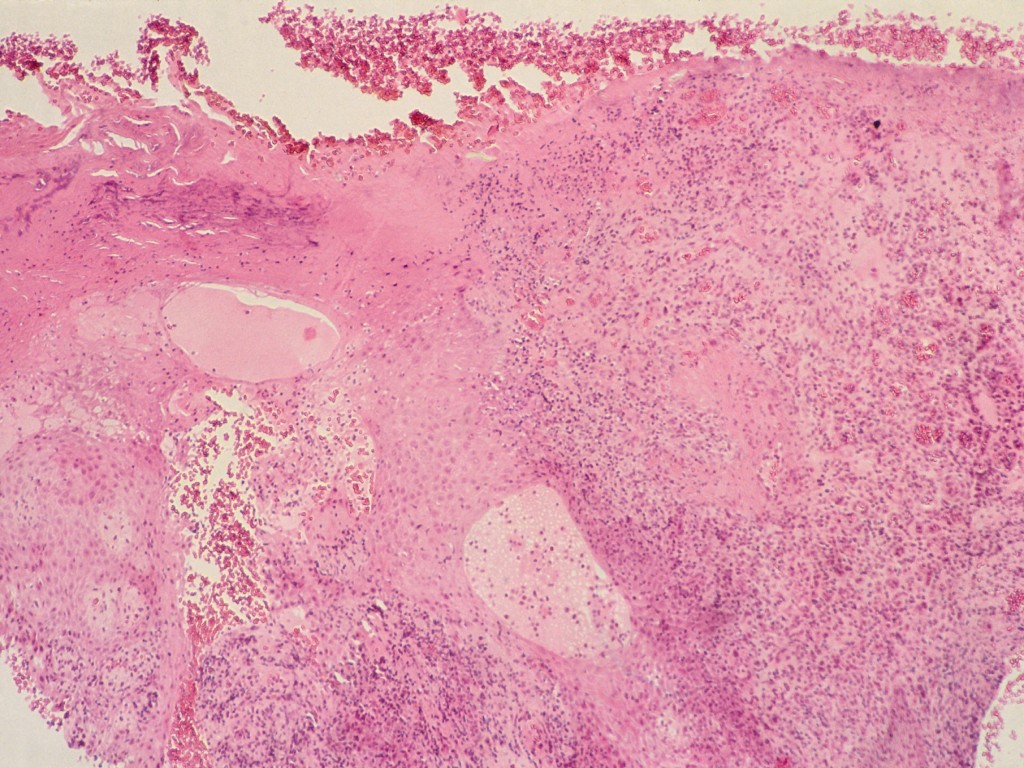

Histologie:

Pseudo-epitheliomateuze hyperplasie, tekenen van virale infectie zoals perinucleaire eosinofiele virusinsluitsels, vacuolaire veranderingen van het epitheel en

pycnotische kernen van keratinocyten. Lymfohistiocytair ontstekingsinfiltraat met plasmacellen.

Histologie van orf (ecthyma contagiosum) Histologie van orf (ecthyma contagiosum) Histologie van orf (ecthyma contagiosum)

histologie van orf histologie van orf histologie van orf